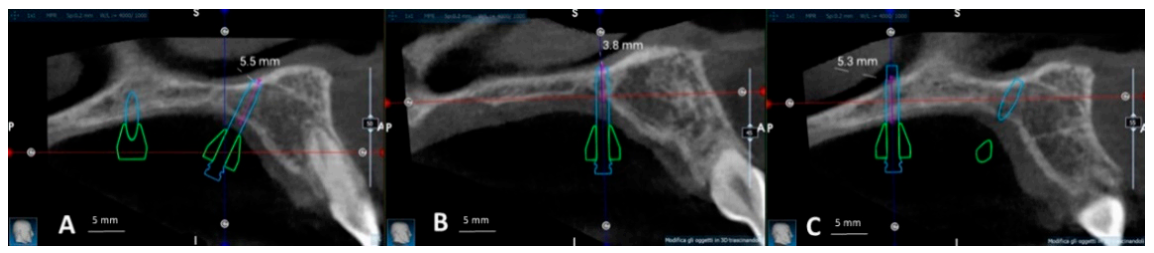

The virtual model of the bushing and miniscrew was then imported into Real Guide software. Three miniscrews with the relative bushings were virtually positioned in the integrated model of the patient maxilla and dental arch. The miniscrew insertion sites were meticulously selected to avoid important anatomical structures like nerves or artery bundles and to maximize the bone thickness at the level of temporary anchorage devices (TADs). Furthermore, the miniscrew bicortical engagement was secured by penetrating the cortical bone layer of the oral cavity vault and nasal floor, to further enforce the TADs primary stability [11], as shown in Figure 5 and Figure 6. Bone thickness at the level of miniscrew insertion sites was measured with the software ruler (Figure 6). These measurements allowed to select the proper length for the miniscrews, that was 13 mm for the anterior right and left ones, and 11 mm for the posterior one. Lastly, the three miniscrews were positioned in a non-parallel way, preferably with divergent apical ends, in order to enhance the vertical stability of the appliance during the clinical use (Figure 1 and Figure 5).

Figure 5.

Bushings and miniscrews positioned in the patient CBCT. (A) Posterior view (B) Lateral view. Bushings and miniscrews are positioned in such a way to achieve miniscrew bicortical anchorage (engagement of cortical bone of oral cavity vault and nasal floor). Also, they are not parallel and preferably diverge apically.

Figure 6.

Measurement of bone thickness at miniscrew insertion sites in the patient CBCT with software ruler, and check of miniscrew bicortical engagement. (A) Anterior right miniscrew. (B) Anterior left miniscrew. (C) Posterior miniscrew.